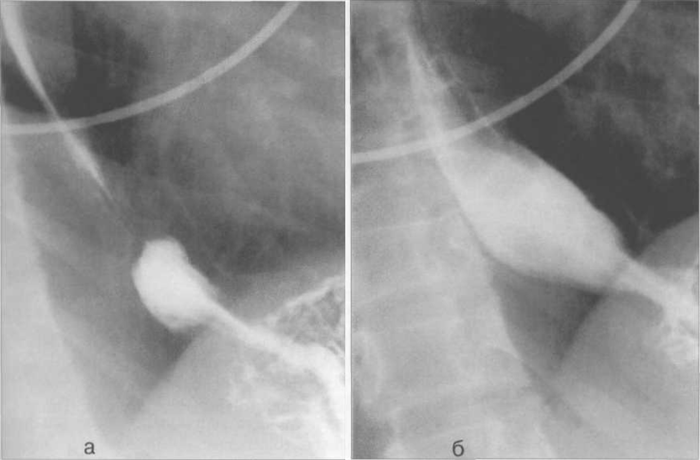

Рис. 11.27. Рентгенограммы пищевода на уровне диафрагмального отверстия.

а — снимок сделан на вдохе; б — снимок сделан на выдохе.

Тонус пищевода оценивают по ширине его просвета, скорости прохождения бариевой взвеси и характеру складок слизистой оболочки. Тонус и эластичность стенок обеспечивают расширение пищевода во время прохождения пищевого комка и сокращение его после опорожнения (см. рис. 11.27). При нормальном тонусе пищевода жидкая бариевая взвесь в вертикальном положении пациента проходит по пищеводу за 3—5 секунд, в горизонтальном — за 8— 10 секунд. Повышение тонуса пищевода сопровождается его укорачиванием, сужением просвета, уменьшением времени прохождения бариевой взвеси, но при резко выраженном повышении тонуса и возникновении спазма это время увеличивается. При пониженном тонусе пищевод удлиняется, просвет его расширяется, время прохождения бариевой взвеси увеличивается.